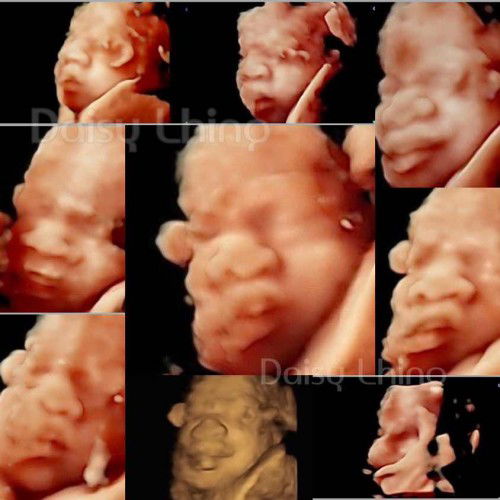

4 D my little gitl. 👧🏻❤️

24 weeks 2 days. ❤️

31 W + 2 D Ultrasound 4D 👶🏻

1,586 g. นน ตามเกณฑ์ สุขภาพดี แข็งแรง หัวใจเต้นดี รอบนี้ให้เห็นแค่ครึ่งหน้าครับ #ทีมลูกชาย

25 Weeks. 👶🏻 Ultrasound 4D.

25Weeks 689g. >> ผู้ชาย 100% 👶🏻 เพิ่มเติมคือ นอนเก่งครับ 😴 #ลูกชายคนแรก #ทีมกันยา